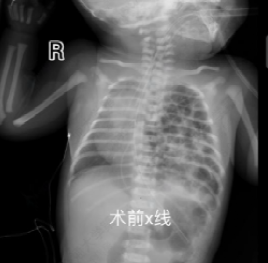

生后24小时,患儿病情逐渐趋于稳定,但影像学提示脾脏、肠管仍大量疝入胸腔,肺组织明显压缩,有可能发生肠绞窄或感染性休克,危及患儿生命。经综合评估后,依据胎儿先天性膈疝临床管理指南(2022),儿外科团队决定实施胸腔镜下膈疝修补术[2]。手术过程中可见脾脏及肠管几乎占据整个胸腔,造成肺组织严重受压。与传统开胸手术相比,胸腔镜具有创伤小、恢复快的优势,但在新生儿中操作空间极为有限,脏器质地柔嫩,手术风险和技术要求显著提高。尤其新生儿脾脏组织异常脆弱,稍微牵拉或触碰即可导致出血,且止血困难,因此操作需慎之又慎。再充分暴露后,曹主任小心翼翼地将腹腔脏器全部还纳后,随后对膈肌缺损进行修补,每一针都精准缝合,避免出现缝隙导致再次疝入,然而,由于缺损面积巨大,无法直接采用折叠缝合方式关闭,因此使用生物补片行加固修补。在麻醉科和手术部护理团队的精密配合下,儿外科团队成功将脏器还纳腹腔并精准修补膈肌缺损,手术顺利完成。术后患儿肺扩张逐渐恢复,呼吸功能改善,成功撤离呼吸机。目前状态良好,已顺利出院。